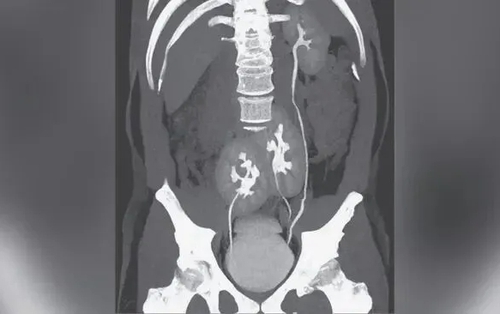

• Đang ăn sữa chua, người phụ nữ nuốt chiếc thìa dài 17cm vào bụng

Đang ăn sữa chua, người phụ nữ nuốt chiếc thìa dài 17cm vào bụng

Một người phụ nữ đã vô tình nuốt phải một chiếc thìa dài 17cm khi con chó của cô nhảy lên đùi trong lúc cô đang ăn sữa chua.